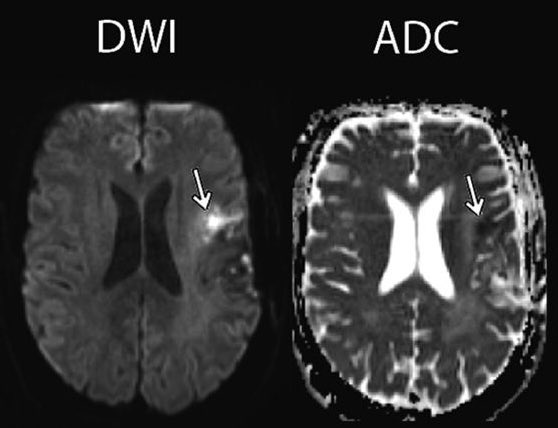

3. DWI*:

bright = abnormal = "diffusion-restricting" = could be hypercellularity, ischemia, demyelination, abscess, &c

**the above applies only if the corresponding area is dark on ADC sequence (if also bright on ADC, then just T2 shine-through)**